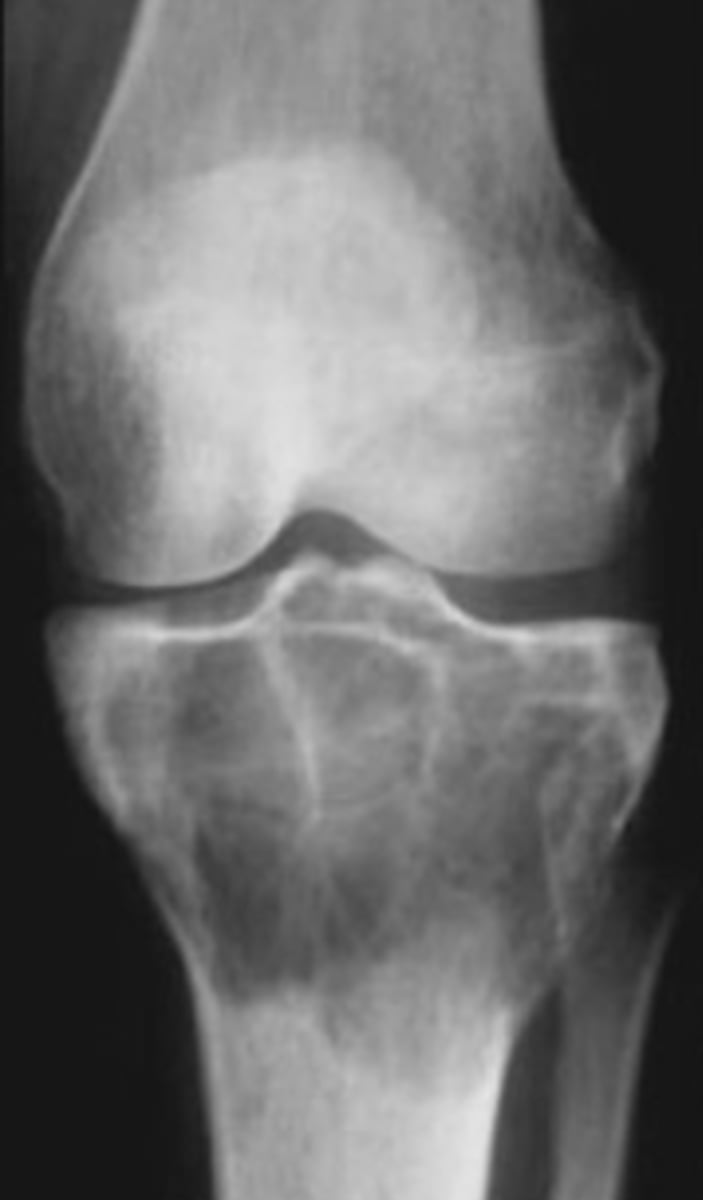

Osteoclastoma

Another term for giant cell tumor

- 80%

- 20%

Giant cell tumor pathology:

- _____ benign (F:M, 3:2)

- _____ malignant (M:F, 3:1)

<p>Giant cell tumor pathology:</p><p>- _____ benign (F:M, 3:2)</p><p>- _____ malignant (M:F, 3:1)</p>

- 20-40 y.o.

- Knee (tibia and femur)

- Localized pain and aching

- Joint pain and restricted motion

State the clinical features of giant cell tumor

<p>State the clinical features of giant cell tumor</p>

4

New cards

- Osteolytic

- Geographic

- Multiloculated and septated

- Begin in metaphysis

- Extend to subarticular bone

- Expansion

- Eccentric

- Quasi-malignant (can't tell benign from malignant)

State the imaging features of giant cell tumor

<p>State the imaging features of giant cell tumor</p>

Biopsy

We need to do a _____ to tell if giant cell tumor is benign or malignant